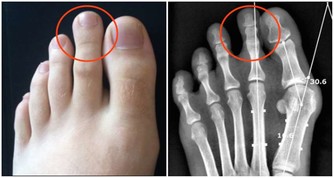

5、肝毒素信號:指甲上有凸起的線

熬夜導致肝臟被迫工作,“肝主筋”,指甲是“筋”的一部分,所以毒素在肝臟蓄積時,指甲上會有明顯的信號。